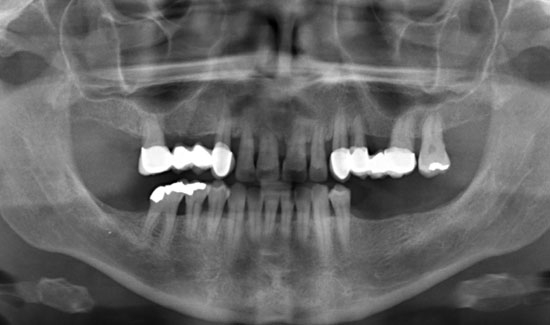

Фиг. 1: Панорамна рентгенова снимка